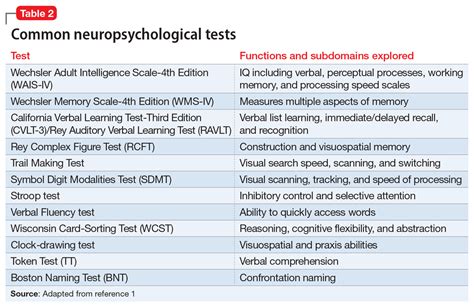

Neuropsychiatric testing encompasses a broad spectrum of methodologies, each with its specific advantages and limitations. One commonly utilized approach is neuropsychological assessment, which explores the connection between brain functions and behavior. This type of testing typically includes a series of cognitive tasks designed to evaluate memory, attention, language, and executive functions. For instance, a neuropsychological test may involve completing puzzles, recalling sequences of numbers, and describing images, which collectively provide a detailed insight into cognitive capabilities.